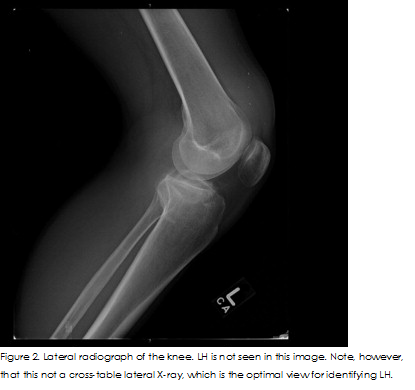

Cause Report

Pallin,2007 and BONNEFOY et at.2006 said that The literature recognises lipohaemarthrosis, as being a dependable predictor of intra-articular fractures. It arises when bones fracture to the marrow, releasing fat from the marrow that escapes into the joint space Conventionally, as lipohaemarthrosis was determined from X-rays as a fat-fluid level on horizontal, cross-table lateral radiographs. However, pursuant to Schick et at.2003 and Aponte EM, Novik JI,2013, it can also be identified through the use of other tomographic and non-tomographic techniques; also there are advantages and disadvantages associated with the different techniques, the Correct diagnosis is important as it determines whether treatment should be surgical or conservative (Schick et at.2003). In ultrasound images, magnetic resonance imaging (MRI) and CT Scan, lipohaemarthrosis can be visualised as a single fluid-fluid level, comprised of fat and blood, or as a double fluid-fluid layer with layers of blood cells, serum and fat (Aponte EM, Novik JI,2013). The fat layer is made up of many fat globules that generate almost no ultrasound echoes. Beneath this is the serum layer, which also does not generate echoes, but the last layer of clotting blood cells does is echogenic (Aponte EM, Novik JI,2013). Intra-articular knee fractures can be distinguished with high specificity by X-rays but the technology has low sensitivity for lipohaemarthrosis. A study revealed that X-rays were unable to detect fat-fluid levels in 65% of patients with intra-articular fractures, but for 100% of the patients with lipohaemarthrosis detected in their X-rays had intra-articular fractures (Aponte EM, Novik JI,2013). Lipohaemarthrosis is reliably identifiable by CT and MRI when X-rays find no indication of fracture. Yet not all patients with knee trauma have access to these diagnostic technologies. Research indicates that the distinctive sonographic pattern of lipohaemarthrosis takes time to emerge (Aponte EM, Novik JI,2013). Using an in vitro blood and oil mix that was subjected to sonography immediately after mixing and thirty mints later, two layers were found in the first image but in the later image, this had increased to three layers. For the clinical aspect of this study, 7 patients whose knee had been immobilised following intra-articular knee fractures received ultrasound scans either twenty mints or three hours after immobilisation. In sex of the patients scanned after 20 min, the effusion appeared as two-layers only. In the patient scanned after three hours, a three-layered effusion was identified (Aponte EM, Novik JI,2013). According to the study conducted by (Bonneyfoy et al.2006) in 2 patients, no lipohaemarthrosis was detected by ultrasound but CT scans revealed they had intra-articular fractures. The sonograms for these patients were performed within two hours of trauma and this may not have been adequate time for lipohaemarthrosis to progress. There are a number of factors, apart from timing, that ought to be considered when attempting to diagnose lipohaemarthrosis by ultrasound. Chief amongst these is it is important not to mistake the normal pad of fat that lies above the knee for the fat layer of lipohaemarthrosis (Aponte EM, Novik JI, e2013). The fat pad is positioned behind the quadriceps tendon and in front of the suprapatellar bursa. Differentiation of these structures can be achieved by squeezing the joint, which in lipohaemarthrosis will cause the layers in the effusion to mix and the image of the fat-fluid level will blur (Aponte EM, Novik JI, e2013). Another cause for lipohaemarthrosis is rupture of the infrapatellar fat pad. Using lipohaemarthrosis to distinguish between a fracture and a fat pad ruptured by trauma is challenging. It is thought that isolated infrapatellar fat pad rupture due to trauma is rare (Aponte EM, Novik JI,2013).